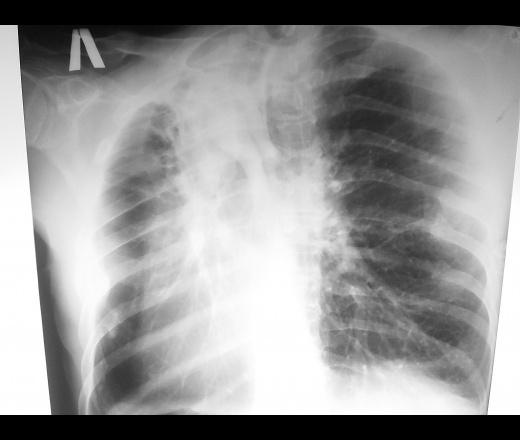

Мужчина 1962 г.р. жалобы слабость,потеря веса килограммов 12 за 2 месяца,температура  37.5 давно. Пьет водку и курит самосад с рождения. На вопрос болел ли тбк говорит не болел. Врет конечно,не знаю зачем. Выяснять не стал в птд отправил. Фиброателектаз это называется коллеги?

Цирроз, наверное.

Туберкулез это. Фкт, если полость есть. Цирротический, если без распада.

+1. Да, картина похожа на цирротический туберкулёз, но для уверенности неплохо было бы сделать Rg-грамму в левой боковой проекции.

Жаль, что нет бокового.  Цирроз. Но, как писал великий патолог Карл Рокитанский, фиброз является ложем рака. Быстрая потеря массы тела на 12 кг - повод думать о развитии рака на фоне фиброза. Показана бронхоскопия. Жду конечных результатов исследований.

Цирротический tbc.

Рёбра ломал справа.

Туберкулёз считается социально опасным заболеванием и давно вышел за рамки неблагополучных слоев населения. Хотя прямого отношения эта микобактерия к раку не имеет, но есть данные, что среди пациентов с туберкулёзом риск рака легкого увеличивается в 11 раз.

Считал и считаю, не микобактерия имеет отношение к раку, а пневмофиброз любой этиологии, как специфической, так и не спецефической этиологии: пневмококковой, стрептококковой,Клебсиеллезной и т.д.Отсюда и риск рака намного выше на фоне любого пневмофиброза( не сторонник по данному случаю). Рубец на коже, легком, желудке, печени, ... .

+1.Есть данные, что на фоне пневмофиброза рак лёгкого развивается в 286 раз чаще, чем на фоне интактной лёгочной ткани.